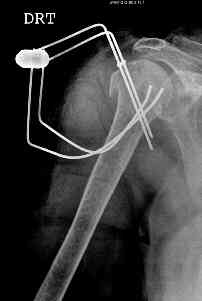

Another option could be closed nailing, see an example, the surgery was done 2 days ago. In common such surgeries are performed under regional anesthesia, not general.

One more option can be fixation by V-shape stressed wires.